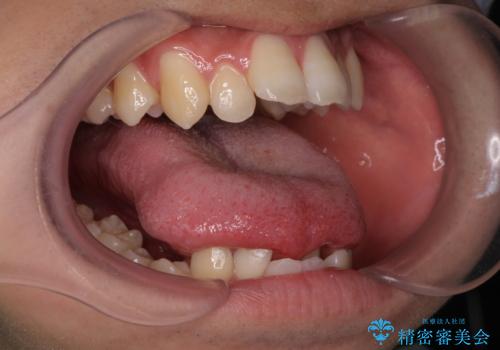

手術は当日に行う事ができ、一週間後に抜糸を行います。

舌の可動域は広がりますがご自身で舌を動かす練習を行わないと滑舌は良くなりません。